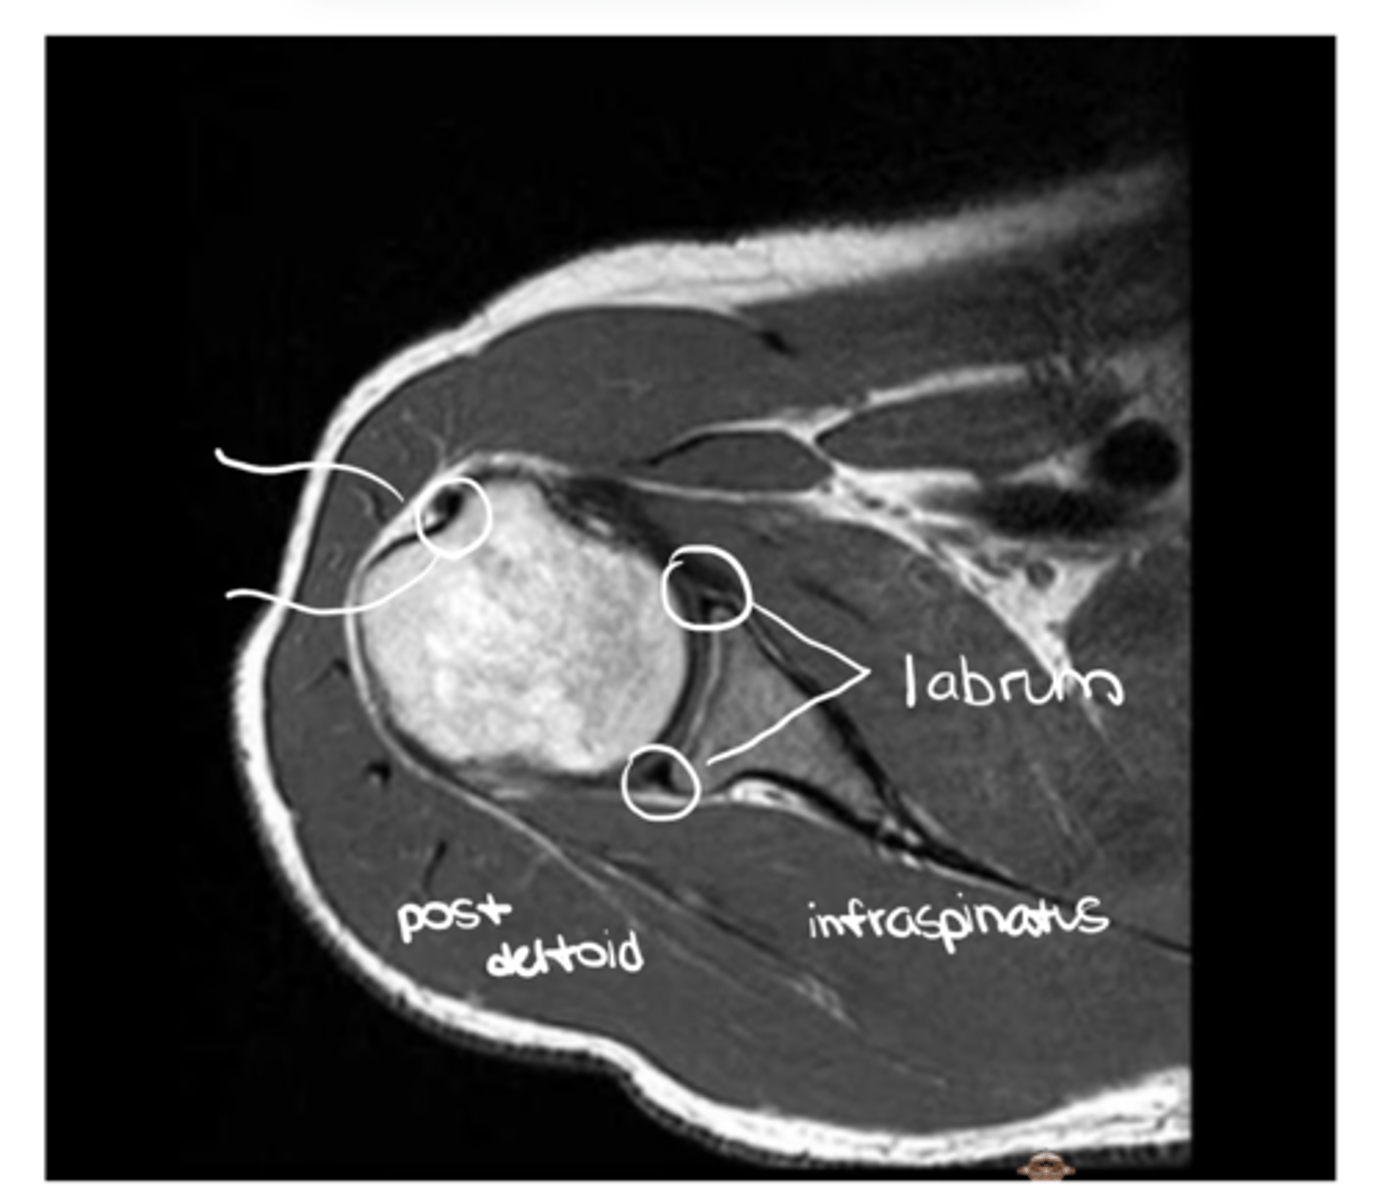

An axial view of the subscapularis tendon wrapping around the anterior portion of the humerus & the infraspinatus tendon on the back side

What is this image depicting?

1. Subscapularis (superiorly)

2. Infraspinatus (inferiorly)

Which structures are being pointed to in this image?